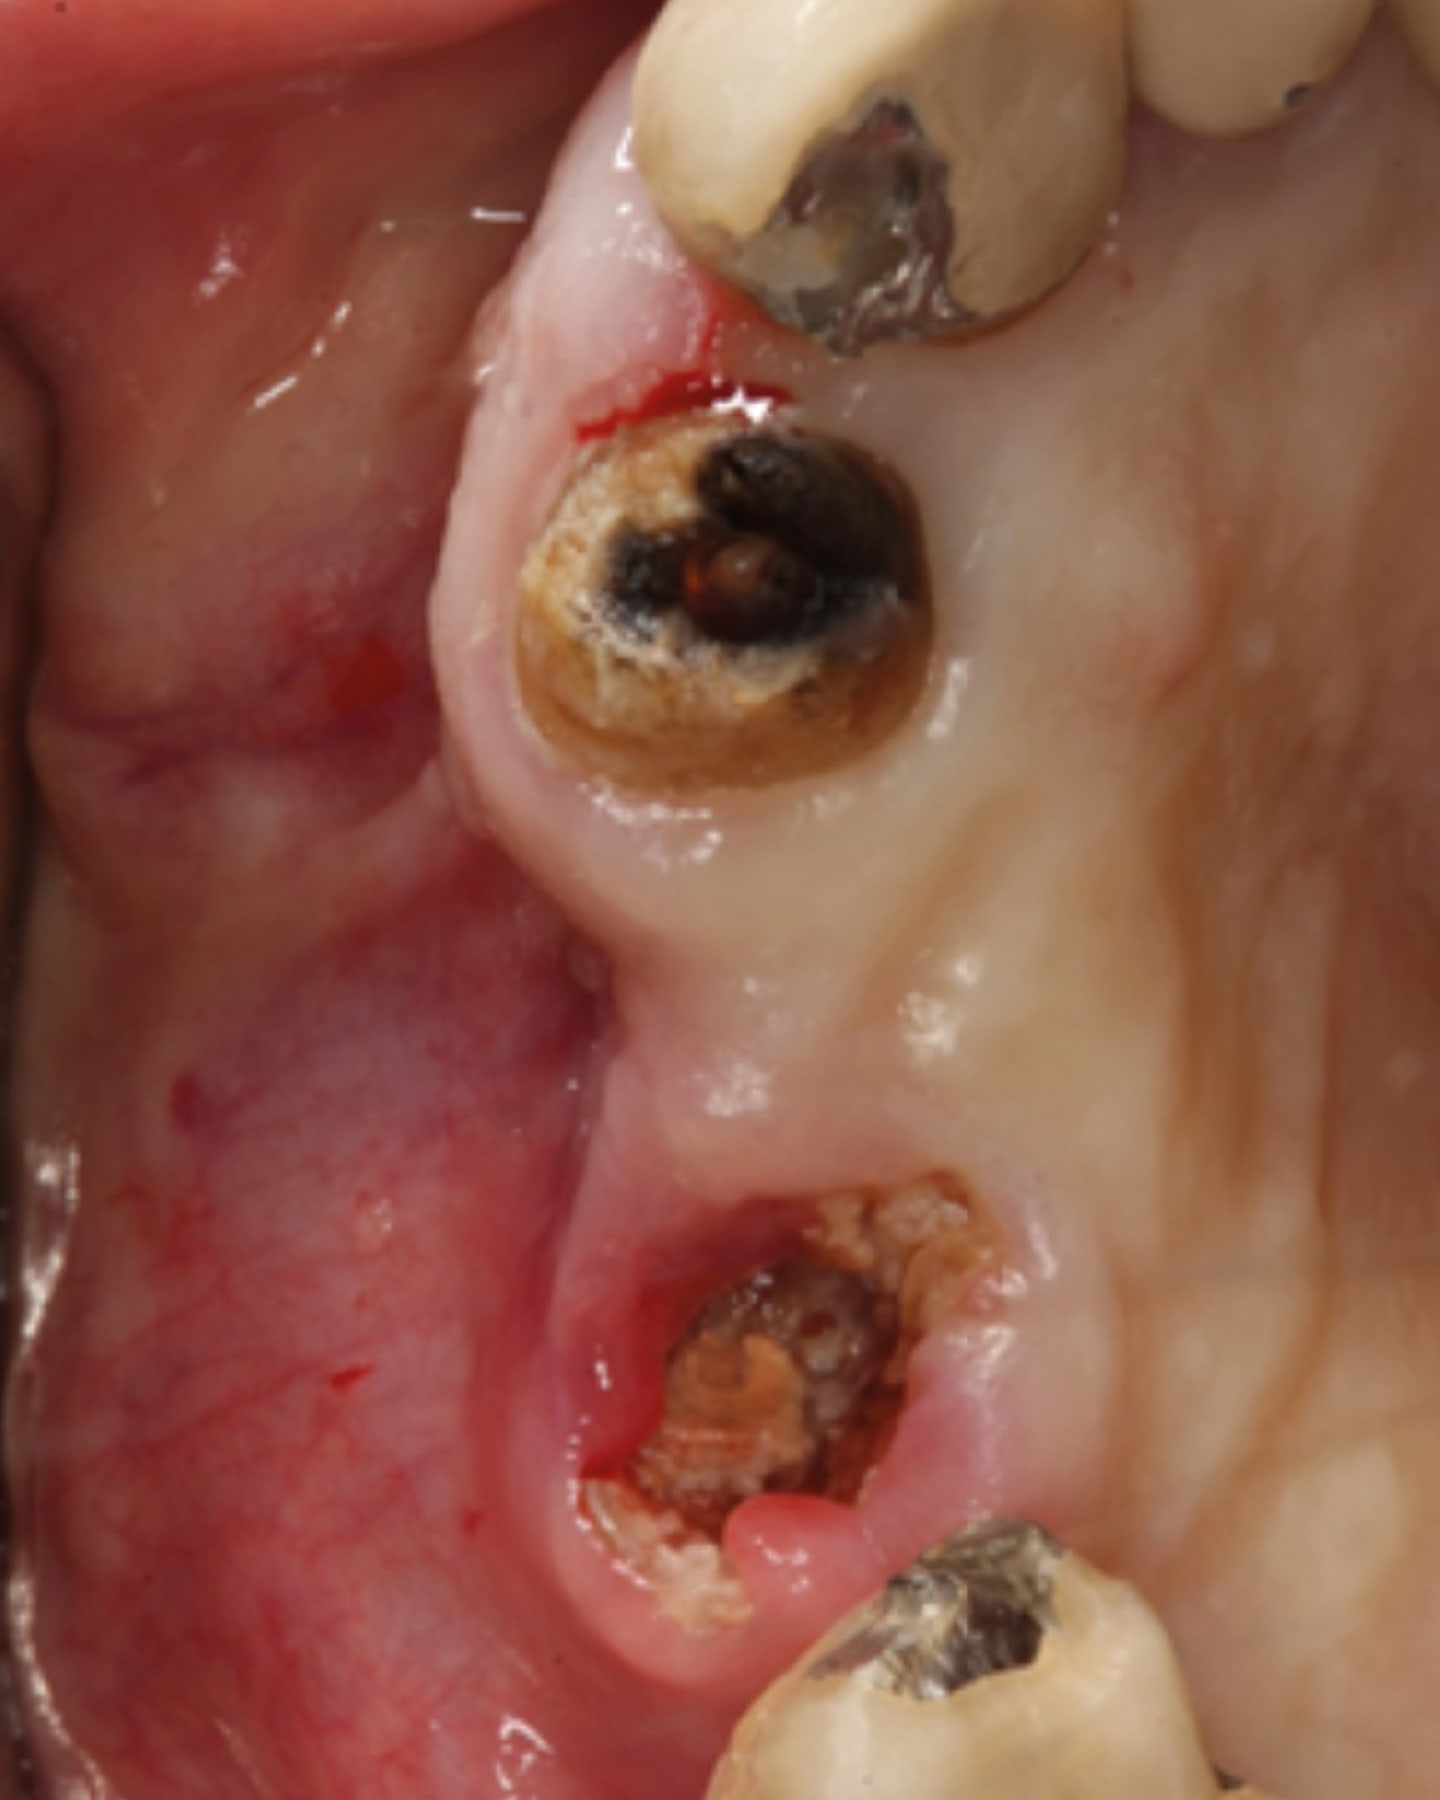

Frequently significant and rapid bone loss occurs following tooth extraction.42,43 Voids created by extraction of teeth either related to periodontal issues, endodontic problems, or structural failure of the tooth will require grafting of the socket to allow implant placement when the void is larger than the intended implant planned for placement. High-frequency vibration has an osteogenic effect, stimulating an increase in vascularization of the clot in the socket or grafting material that had been placed. This also applies to graft placement adjacent to teeth or implants, accelerating host conversion of the graft and angiogenesis of the area.

LMHFV may be used to enhance the graft site healing as such: Following extraction of the problematic teeth the sockets are curetted to remove any residual pathologic tissue. The extraction sockets are filled with an appropriate graft material and the site closed with or without a membrane. A radiograph taken at graft placement will demonstrate a granular appearance with lower density than the host’s adjacent bone. The LMHFV device is utilized by the patient for 5 minutes daily over a 4-month period. When examined radiographically, the grafted site typically demonstrates conversion of the graft particles to blend with the surrounding host bone with similar radiographic density, appearing ready for implant placement. Flapping of the previously socket-grafted site will demonstrate fill of the voids and bone fill earlier than what would be observed if LMHFV was not utilized.

A 76-year-old male patient presented for extraction of the non-restorable teeth in the right maxillary arch. Examination noted a fixed bridge from the right maxillary 1st molar to the right central incisor, and the bridge exhibited Class II mobility. The clinical presentation and findings were discussed with the patient, and a treatment plan involving extraction of teeth, socket grafting, and, following site healing, placement of implants.

The bridge was sectioned and removed (Figure 3). The 1st molar, residual root at the 2nd premolar, canine, and central incisor were atraumatically extracted. The extraction sockets were cleaned and debrided (Figure 4). A block was fabricated from L-PRF derived from the patient’s blood and combined with cortico-cancellous bone (Maxxeus, Kettering, Ohio). The extraction sockets were filled with the graft, and edentulous areas were grafted to restore ideal volume (Figure 5). A BioXclude amnion-chorion barrier membrane (Maxxeus) was placed over the graft material, tucked under the flap margins, and the site was closed with PGA sutures (Figure 6). The patient was provided with a PTech LMHFV device and instructed to use it twice daily for the recommended 5 minutes each session and continue until returning for the post-operative appointment.